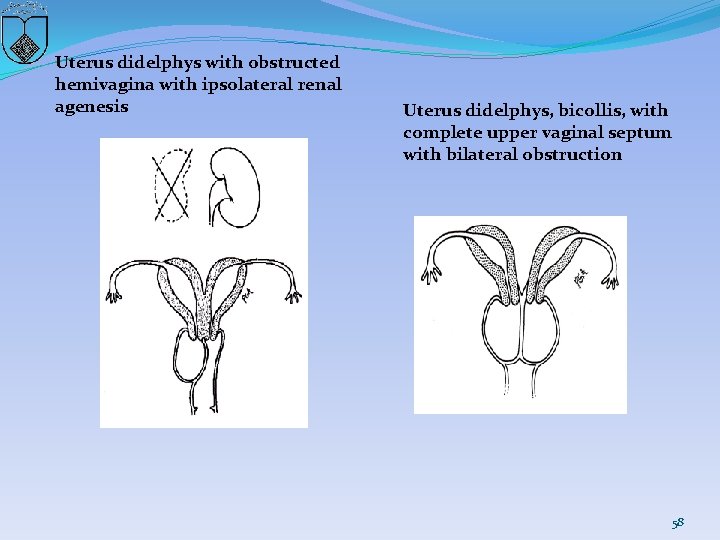

Uterus didelphys with obstructed hemivagina with ipsolateral renal agenesis Uterus didelphys, bicollis, with complete upper vaginal septum with bilateral obstruction 58